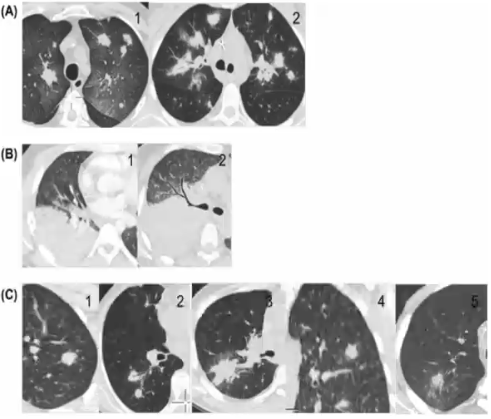

❖ CT平扫(结节、肿块样、实变、磨玻璃影、晕征、反晕征等)

❖ CT增强(强化程度,低密度征)

❖ CTPA:结节或肿块样病变内血管改变